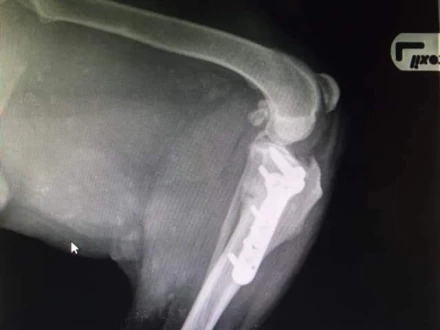

Operacje ortopedyczne:

Specjalizujemy się w szerokim zakresie operacji ortopedycznych, obejmujących leczenie złamań, problemów ze stawami, w tym operacje rekonstrukcyjne. Nasze zaawansowane techniki chirurgiczne zapewniają precyzyjne leczenie urazów i chorób układu ruchu.

Leczenie zerwanego więzadła krzyżowego:

Oferujemy różne techniki leczenia zerwanego więzadła krzyżowego, w tym TPLO (Tibial Plateau Leveling Osteotomy), CWO (Cranial Wedge Osteotomy) i TTA (Tibial Tuberosity Advancement). Te zaawansowane metody chirurgiczne pomagają przywrócić funkcję stawu i poprawić komfort zwierzęcia.

Metoda TPLO